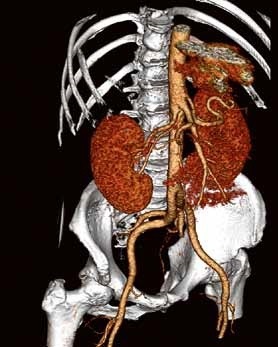

Die Klinik verfügt über 14 Computertomographen (CT), zwölf Magnetresonanztomographen (MRT) sowie zahlreiche Ultraschallgeräte. Allein am Campus Benjamin Franklin führen die Radiologen an sieben Tagen die Woche je zwischen 50 und 60 CT Untersuchungen täglich durch. Seit knapp drei Monaten steht ihnen dazu der neue 160-Schicht-Low-Dose-CT Aquilion PRIME zur Verfügung. Ein weiterer Aquilion PRIME sowie ein 640-Schicht-Volumen-CT Aquilion ONE ViSION EDITION wurden am Campus Mitte installiert. „Als wir nach einem neuen CT gesucht haben, war klar, dass dessen Ausstattung allen universitären diagnostischen Anforderungen gerecht werden muss", erklärt Dr. Stefan Niehues, Radiologe und Oberarzt der Klinik für Radiologie am Campus Benjamin Franklin.

„Mit dem neuen CT Aquilion PRIME können wir das komplette radiologische Spektrum der Charité abdecken. „Die gesamte Polytrauma-Diagnostik über die Akutversorgung bis hin zur Neuroradiologie und Diagnostik bei jungen Menschen führen wir mit dem Aquilion PRIME durch."

Neben der Rechnergeschwindigkeit lautet das Schlüsselwort bei dem neuen Gerät „Adaptive Iterative Dosis-Reduktion (AIDR 3D)". „Dieser mathematische Algorithmus erlaubt es uns, mit einem Bruchteil der Dosis zu arbeiten, die wir bisher für die erforderliche Bildqualität benötigt haben", weiß der Radiologe.

„Durch die Spitzentechnologie können wir bei gleich hoher Bildqualität die Dosis an Röntgenstrahlung bei vielen Untersuchungen auf ein Drittel reduzieren."

Darüber hinaus bietet der Aquilion PRIME neue Untersuchungsmöglichkeiten, wie die Body-Perfusion und Dual-Energy, die bald eingesetzt werden sollen.